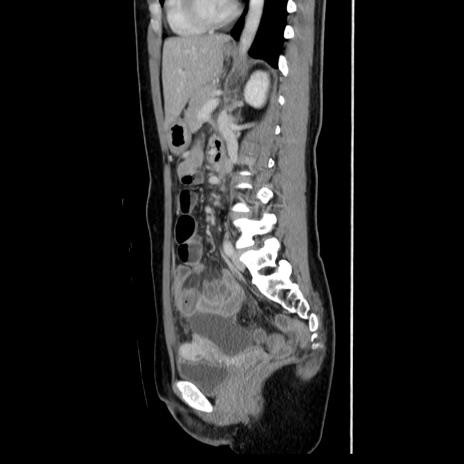

症例39(矢状断像)

【症例】40歳代女性

【主訴】上下腹部痛

【現病歴】2日目から下腹部痛あり。夜間は痛みで眠れなかった。昨日より上腹部痛と下痢が出現。臥位で痛みは軽快したため、休んでいた。本日になって臥位でも立位でも痛みが強くなってきたため救急要請。

【既往歴】子宮内膜症

【身体所見】部:平坦・軟、左上下腹部に圧痛あり、反跳痛あり。

【データ】WBC 21800、CRP 26.78

CT